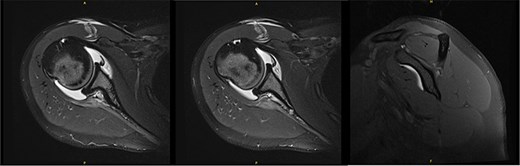

Six years following decompression, the patient presented for right shoulder pain and fatigue without new injury. Post-collegiately, she coached volleyball. MRI revealed a diffusely atrophic infraspinatus muscle belly (Fig. 3). On examination, she demonstrated persistent diminished infraspinatus, supraspinatus, and teres minor strength, pain in the Aber position, mild anterior apprehension, and a positive (+1) Sulcus sign. She proceeded with posterior capsular stretching and cuff strengthening.

MRI 6 years after decompression revealed a diffusely atrophic infraspinatus muscle belly.